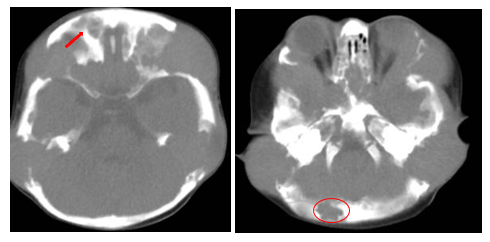

A subsequent CT scan of the brain, complete abdomen, and thorax showed soft tissue lesions that were homogeneous, well defined, and exhibited mild enhancement with contrast, eroding and altering the morphology of the skull cortex without infiltrating the brain parenchyma (Figure 2A & 2B). Additionally, multiple lytic lesions were identified in the sphenoid bone and vertebral bodies of C2, C3, and C5 vertebrae. Thoracic CT revealed lytic lesions in the vertebral bodies of T1, T3, T4, T6, and T7, along with pathological fractures of T5 and T9 (Figure 3A & 3B). Given the extensive bone involvement, the possibility of aggressive systemic disease was considered, including LCH, neuroblastoma, and metastatic rhabdoid tumors. Definitive histopathological examination of the previously biopsied tissue, complemented by immunohistochemistry, confirmed the diagnosis of Langerhans cell histiocytosis (LCH). Immunohistochemical staining was positive for S-100, CD68, PD-L1, and CD1a, which further confirmed the diagnosis. Due to the patient developing bilateral ear discharge, a mastoid CT scan was performed. The scan showed a loss of normal mastoid morphology with bony erosion caused by homogeneous soft tissue lesions bilaterally (right mastoid: 2.9 x 1.8 cm, left mastoid: 3.4 x 2.3 cm) (Figure 4A & 4B). These findings are consistent with the systemic spread of LCH, which affects the temporal bones.

Figure 3A&3B Thoracic CT of the patient revealed lytic lesions in the vertebral bodies of T1, T3, T4, T6, and T7, along with pathological fractures of T5 and T9.